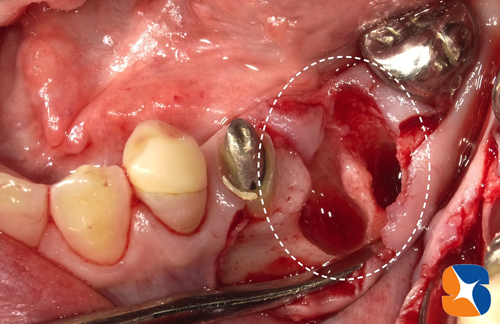

CT撮影での予測通り、ほっぺた側の骨を中心に大きく欠落していました。

この状況の中で、インプラントを的確な位置に、確実に植立します。

同時に、点滴中の患者様のルートより採血させていただきます。CGFと呼ばれる加工細胞を製造して、人工骨と混ぜ合わせ、再び顎骨を回復させていきます。

シュミレーション通り正確にインプラントを植立できました。あとは、骨の欠落部に、CGFと人工骨の一塊をやさしく添加すれば施術は完了です。